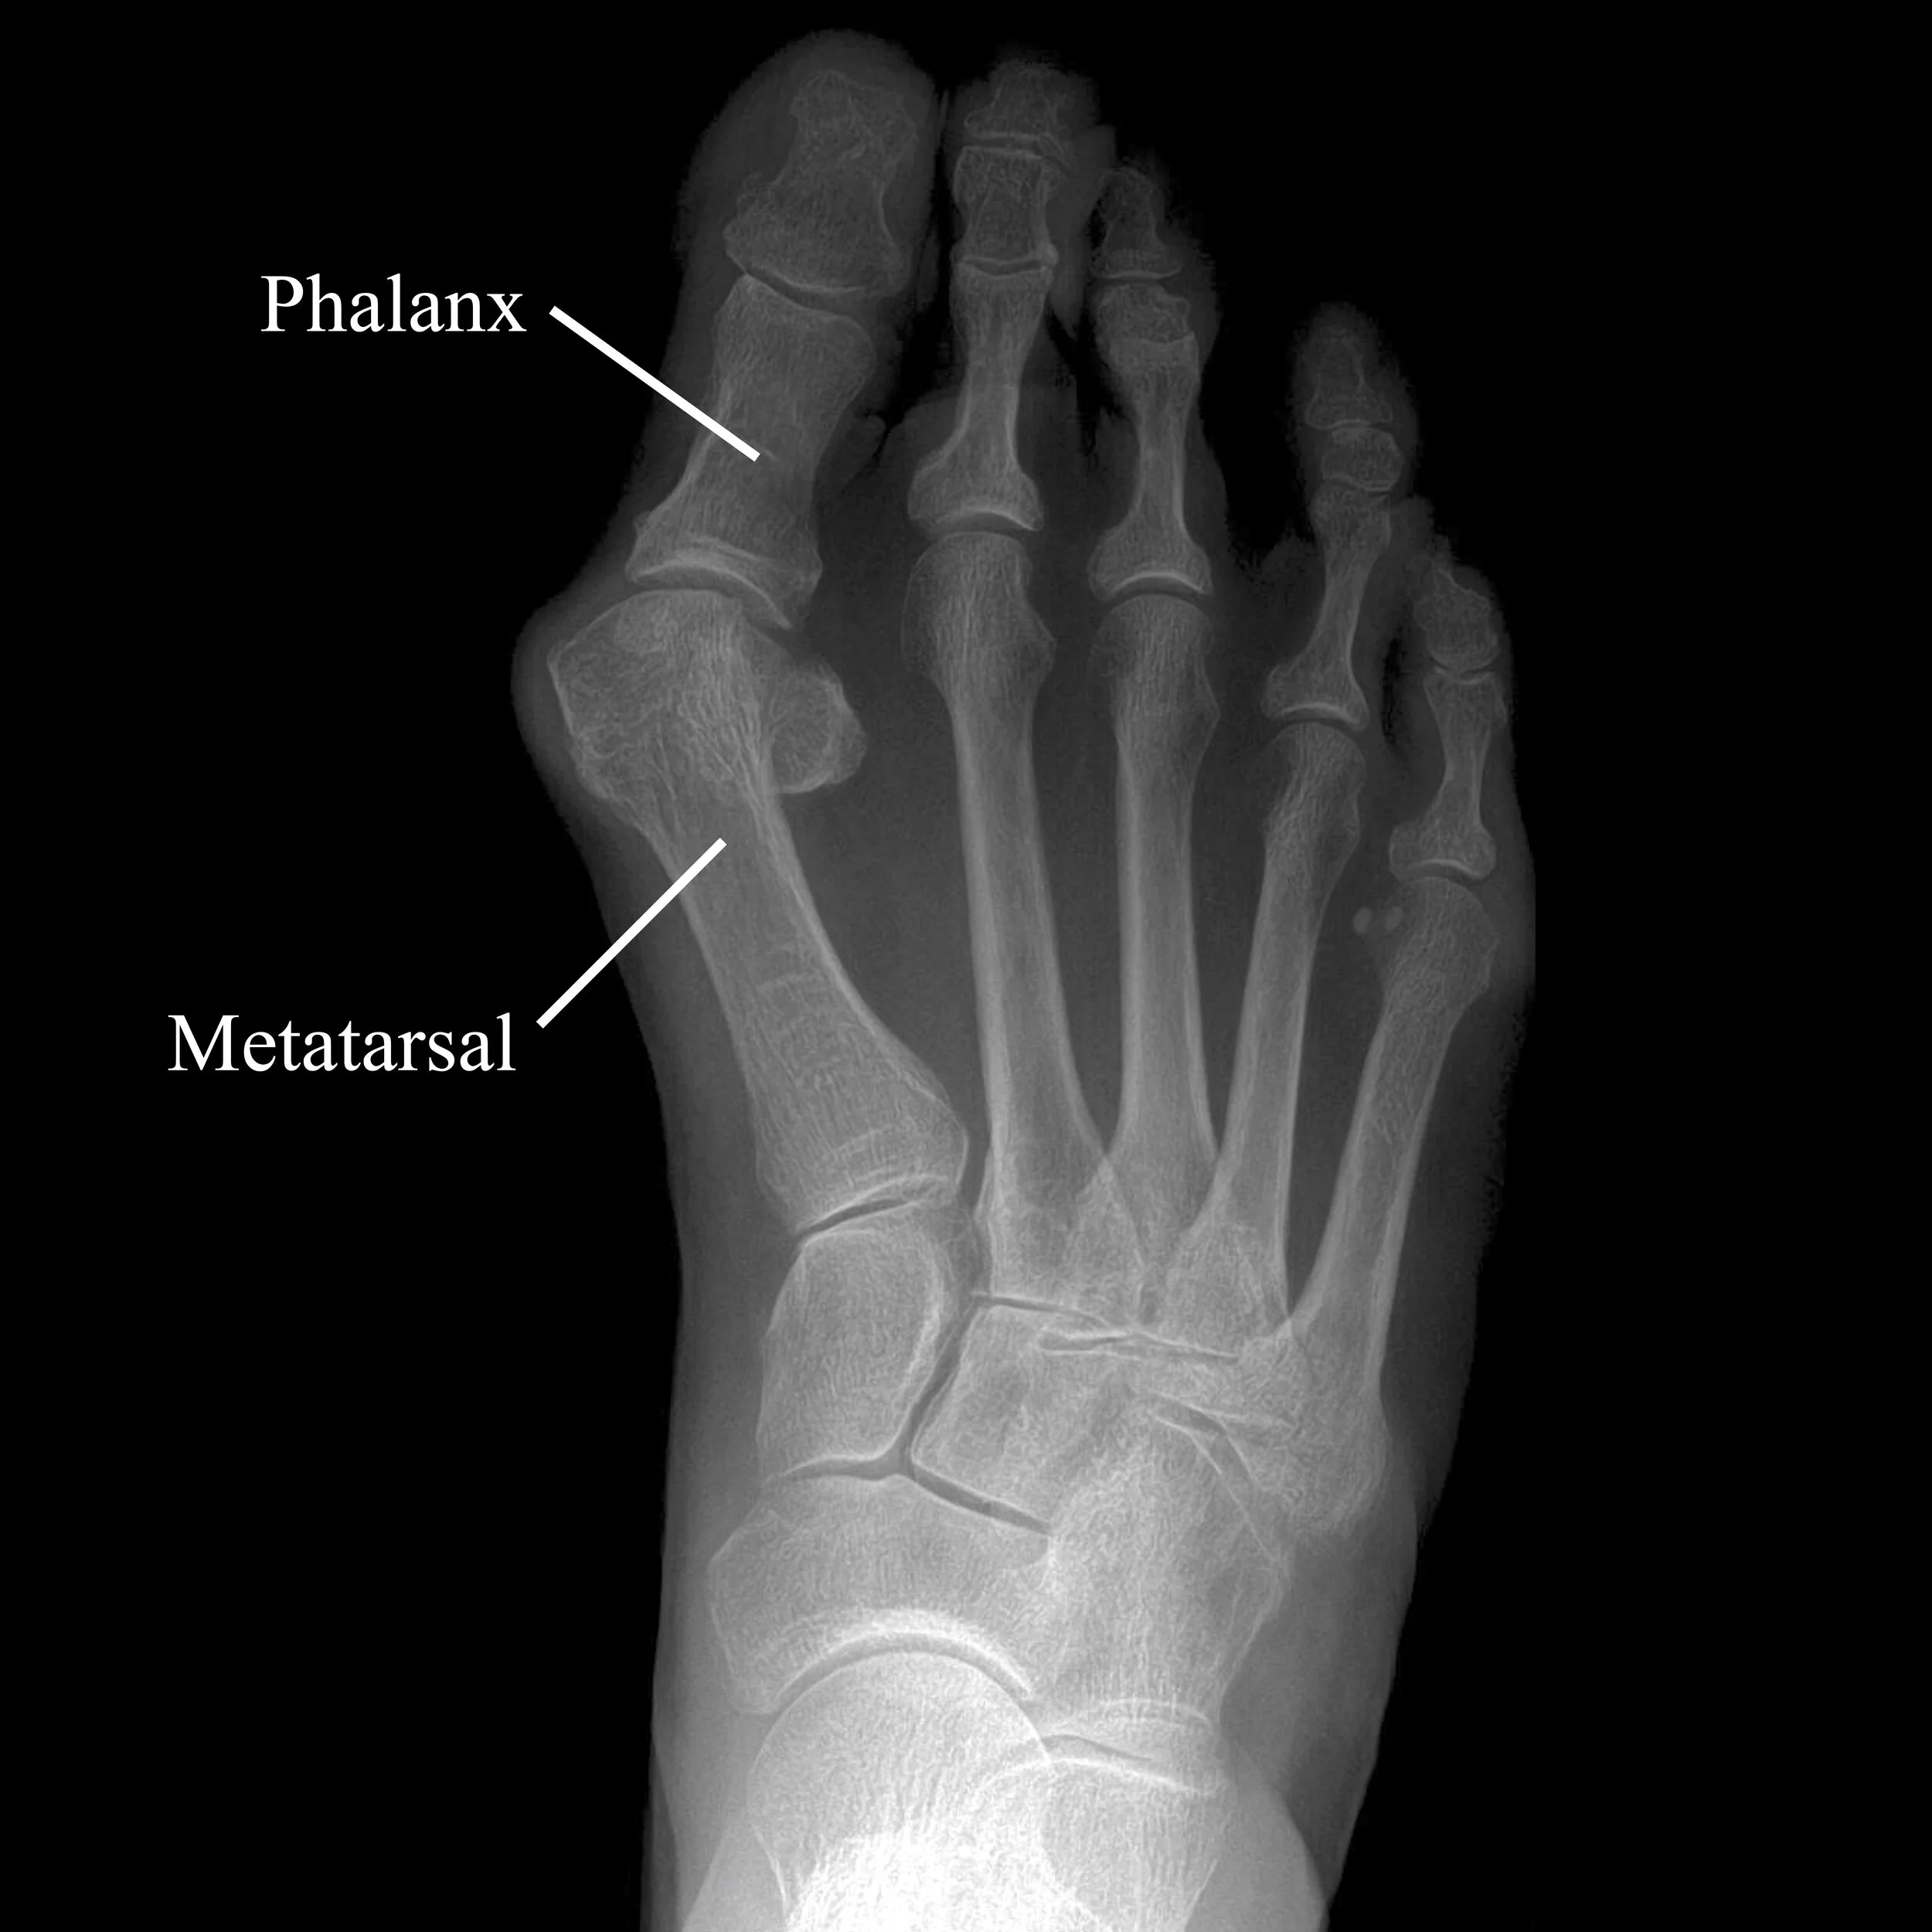

Bunions result from an angular deformity between the metatarsal and the phalanx of the big toe. Specifically, the metatarsal (foot bone) angles outward (towards your other foot), while the phalanx (toe bone) angles inward (towards the smaller toes).

This angular deformity gives rise to the bump where the bones meet, right at the base of the big toe. This bump can become very painful and cause severe problems with shoe wear and walking. It can also cause problems with the smaller toes (hammertoes). Fortunately, a good surgery can reliably correct any bunion deformity and relieve symptoms.